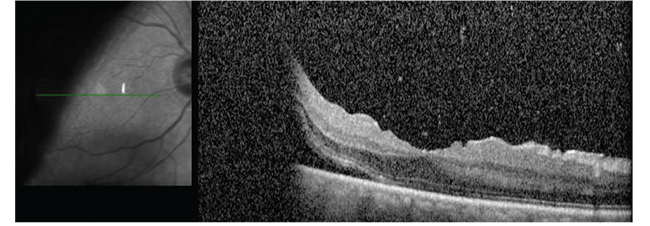

| Figure 1. Preoperative wide-angle color photograph shows a retinal detachment with a giant retinal tear in a 66-year-old pseudophakic man. He experienced a shadow in the vision of his right eye for a week. Visual acuity was 20/30 OD, 20/25 OS. Optical coherence tomography preoperatively shows that the fovea is still attached. |